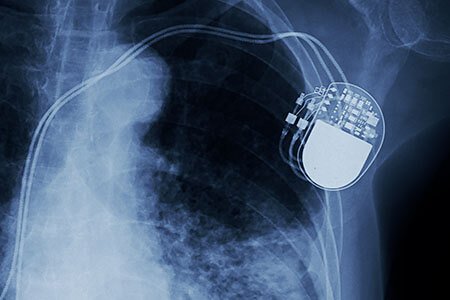

पेसमेकर: पेसमेकर एक इलेक्ट्रॉनिक उपकरण है, जो एक विशिष्ट तरीके से दिल की धड़कन की सहायता करता है। इसमें कुछ इंसुलेटेड तार, बैटरी और एक सर्किट है, जो हृदय में विद्युत आवेगों को नियंत्रित करने के लिए प्रोग्राम किया गया है। इसे हृदय रोग विशेषज्ञ द्वारा शल्य चिकित्सा द्वारा छाती में कॉलरबोन के नीचे लगाया जाता है। पेसमेकर को अस्थायी या स्थायी रूप से प्रत्यारोपित किया जा सकता है और अस्पताल के डॉक्टर द्वारा इसकी निगरानी की जा सकती है या नहीं भी की जा सकती है।